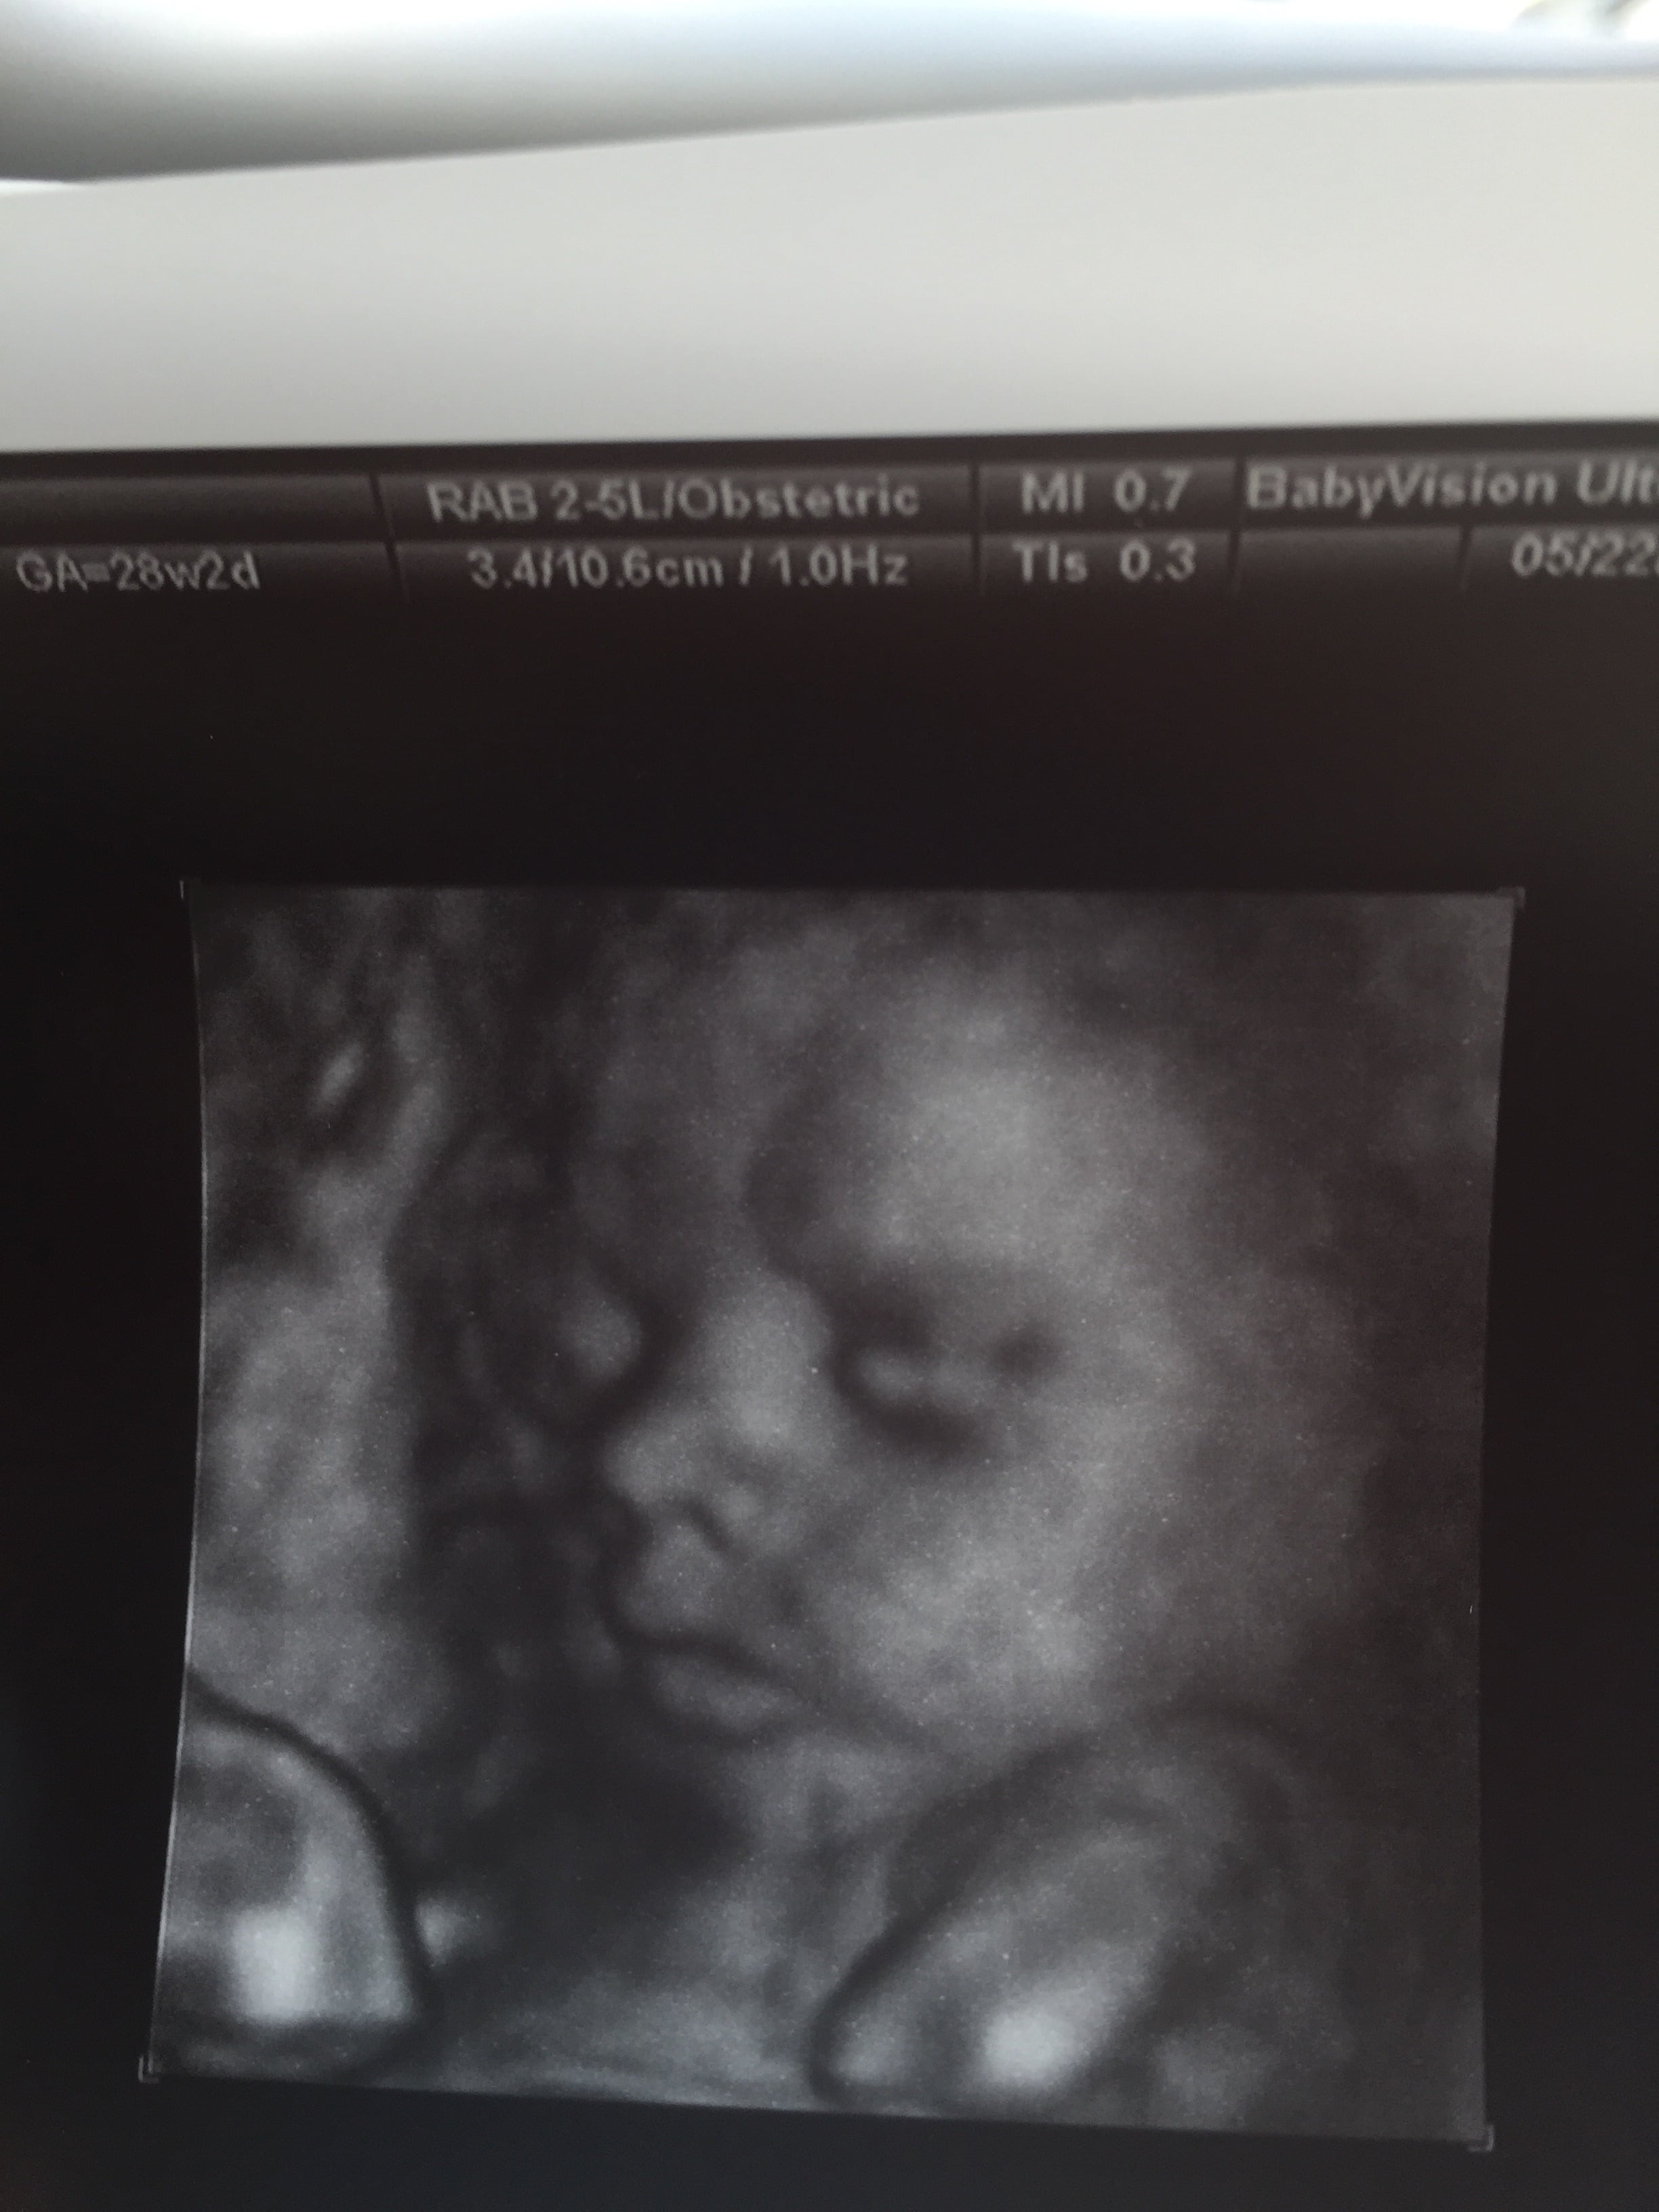

Share your 3D pics!!!!